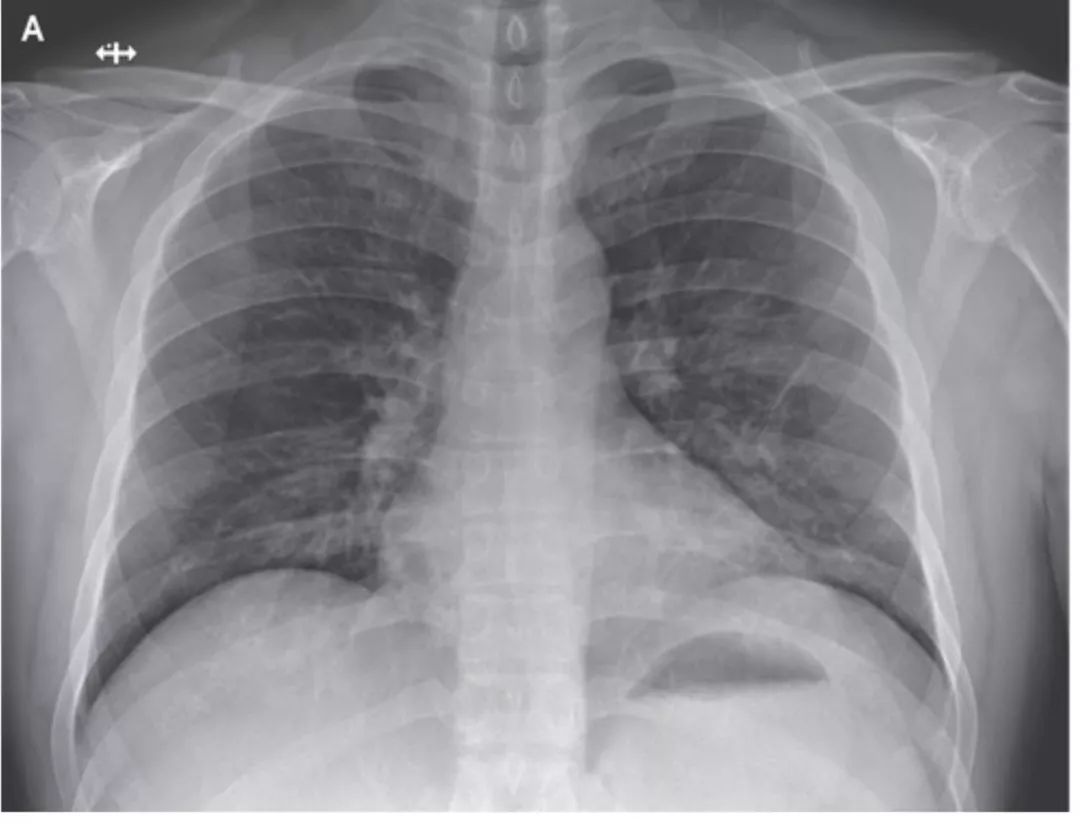

图 9 mpp 的胸盘胸片及 ct 表现.a:胸片示右下肺叶渗出.

(a) 最初的胸片显示双肺广泛的斑片状实变(箭头)和空气支气管征(箭头)

(上) 最初的胸片显示两肺广泛的斑片状实变(箭),空气支气管征(箭头)